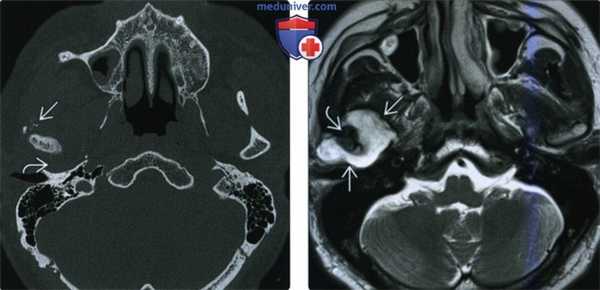

(Слева) КТ в костном окне, аксиальная проекция. Типичная хондросаркома левого височно-нижнечелюстного суаава. Мыщелок нижней челюсти склерозирован и имеет неправильную форму, внутри и вокруг сустава рассеянны множественные кальцификаты. И хотя в данном случае достаточно сложно дифференцировать заболевание от синовиального хондроматоза, в обоих случаях лечение должно быть хирургическим, а точный диагноз будет установлен после гистологического исследования.

(Справа) Реконструкция в сагиттальной плоскости, этот же пациент. Мыщелок деформирован, а часть кальцификатов находится в мягких тканях вне сустава.